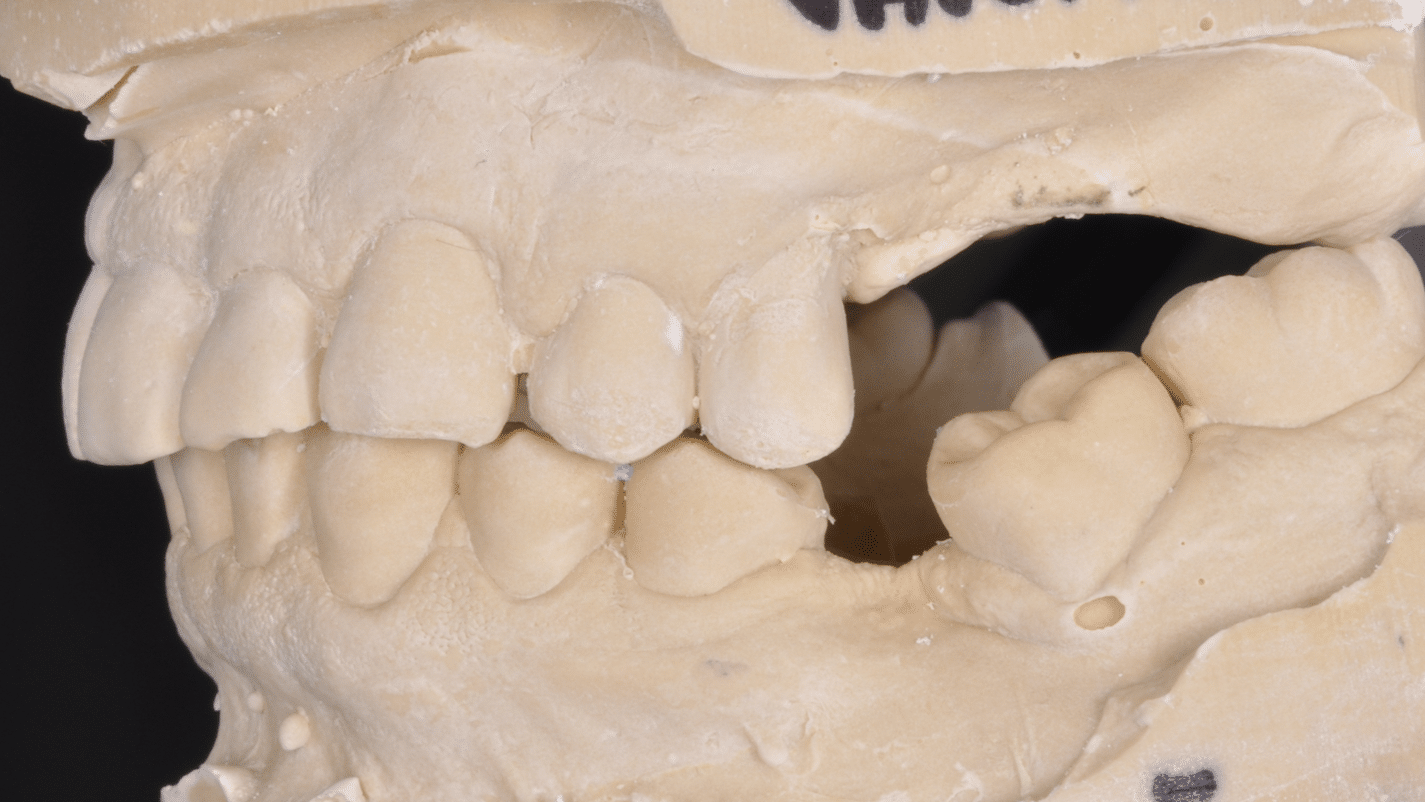

Împreună cu pacientul, am optat pentru inserarea implantelor cu ajutorul ghidului chirurgical pentru a plasa implantul în poziția protetică ideală și pentru a permite realizarea coroanelor insurubate pe implant. A fost efectuată scanarea digitală a arcadelor și a ocluziei pacientului, iar împreună cu tehnicianul radiolog de la DigiRay a fost suprapus fișierul .stl al amprentei digitale peste fișierul .dcm de la CBCT, utilizând software-ul 3Shape.

S-a planificat individual poziția și axul de inserție al fiecărui implant.